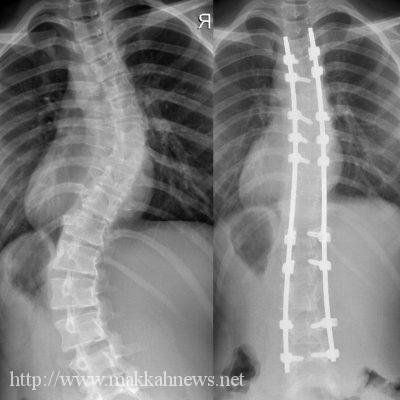

ضمن خططها الاستراتيجية في تقديم خدمة طبية تخصصية ونوعية شرعت مدينة الملك عبدالله الطبية بالعاصمة المقدسة ممثلةً في قسم جراحة العمود الفقري مؤخراً في العمل بتقنية حديثة على مستوى الشرق الأوسط وتعد من التقنيات الأحدث على مستوى العالم تسمى less invasive surgery in idiopathic scoliosis

تتمثل في تدخل جراحي محدود لعمليات جنف العمود الفقري معتدل ومتوسط الشدة تقوم على أساس تعديل وتثبيت سلسلة فقرات الظهر وتقويم الانحراف بأجراح صغيرة متعددة في الظهر بديلة للعملية التقليدية لفتح الظهر كاملا .

وأضاف ، بأن المدينة الطبية اجرت ( ٤ ) عمليات ناجحة ولله الحمد حيث استقبلت المدينة الطبية احدى الحالات لشاب يبلغ ال ١٨ من العمر كان يعاني من تقوس الظهر في منطقتين من العمود الفقري وبعد عمل الفحوصات والأشعات الأساسية قرر الفريق الطبي اجراء عملية الجنف بهذه التقنية حيث تم تجهيز المريض وادخاله غرف العمليات واحتاج معها الى أربعة جروح صغيرة لتعديل الانحراف وتكللت بالنجاح ولله الحمد وتمت متابعة المريض لمدة أسبوع من العملية بدون ان يكون في حاجة لمسكنات للألم ولله الحمد وتمت متابعته بالعلاج الطبيعي وهو يتمتع الان بكامل الصحة والعافية.

والجدير بالذكر ان هذه العمليات تستخدم لحالات الجنف الخفيف والمتوسط الشدة اما في حال زاد التقوس عن ستين درجة فغالبا فتح الظهر بالكامل هو الأنسب والانجح طبياً.